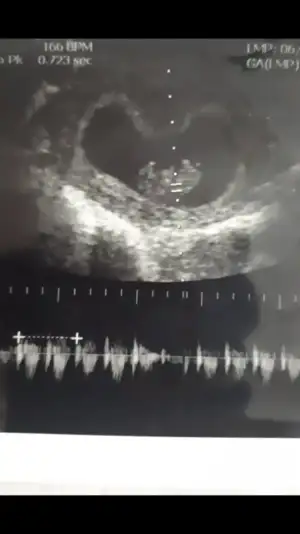

ikra meyra sence cinsiyet nedir😊

• 15653757608708562029668534214349.webp

15653757608708562029668534214349.webp

36,5 KB · Görüntüleme: 69